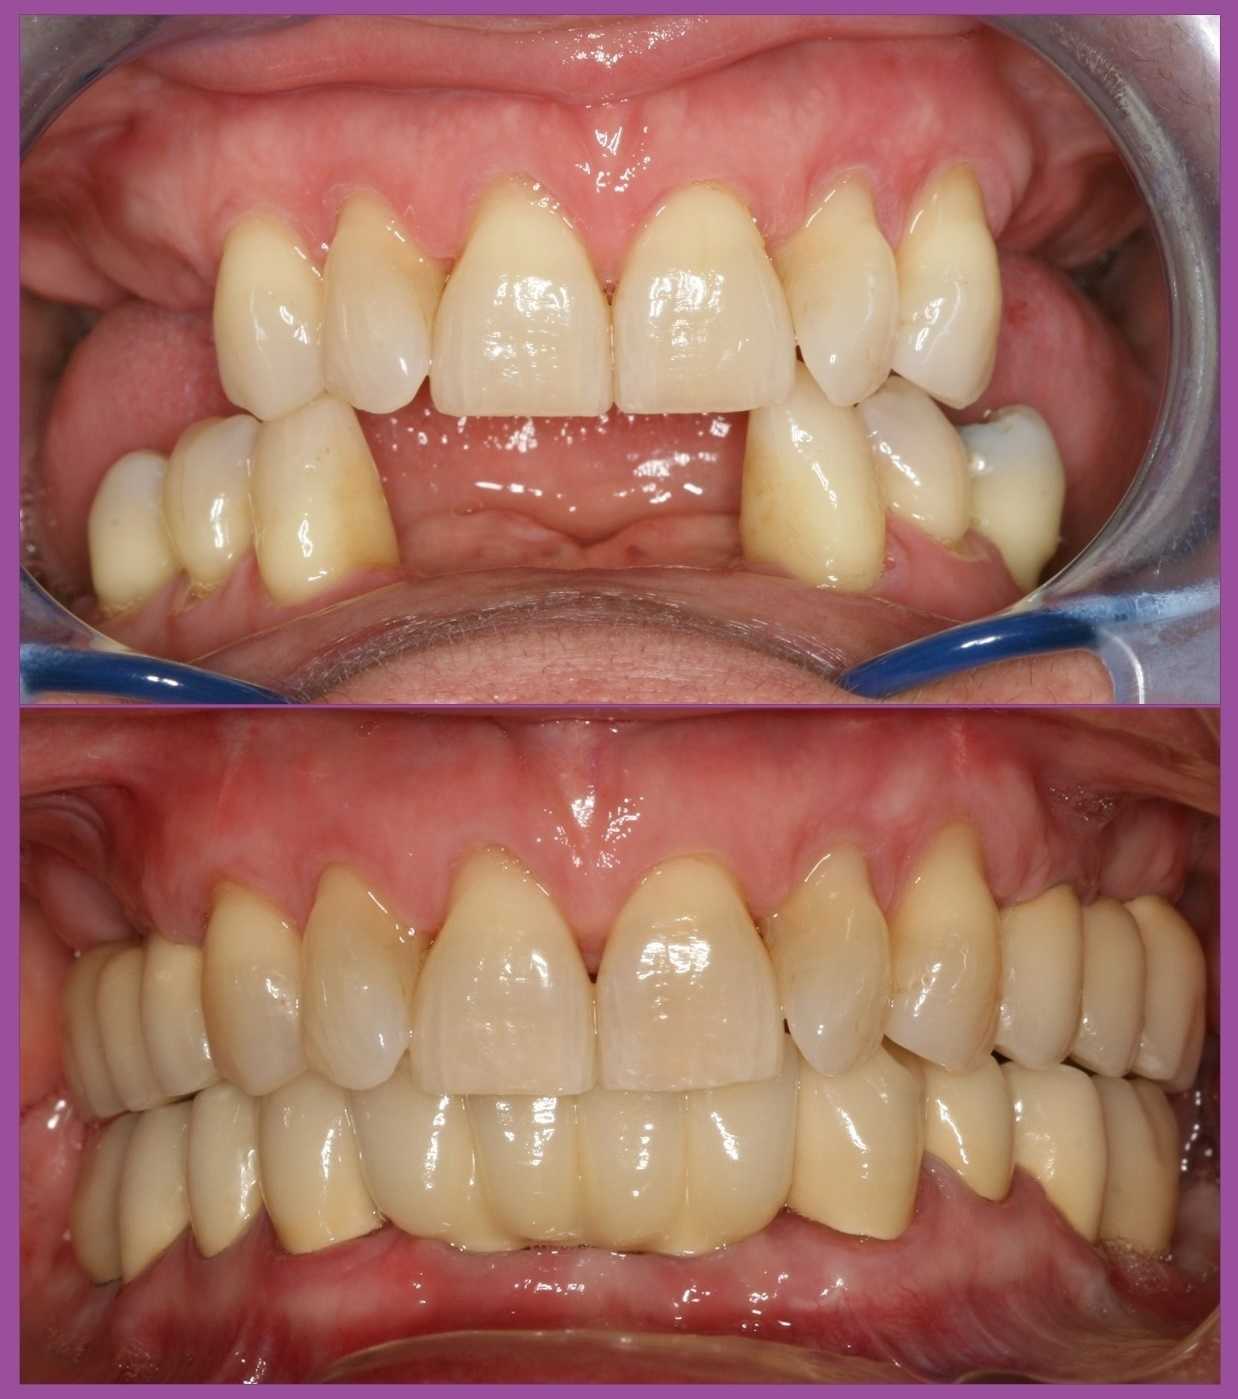

Miután sikerült a fogágypusztulást megállítani, és ezt az állapotot stabilizálni, megtörtént a foghiányok végleges pótlása implantátumok és fémkerámia fogpótlások segítségével. Ezalatt a pácienssel és a dentálhigiénikus kolléganővel közösen kialakítottunk egy olyan fogmosási rutint, amellyel a hölgy fenn tudja tartani a gyulladásmentes állapotot.

Páciensünk végtelenül elégedett volt a végeredménnyel, és azóta is rendszeresen látjuk az ellenőrzések során.